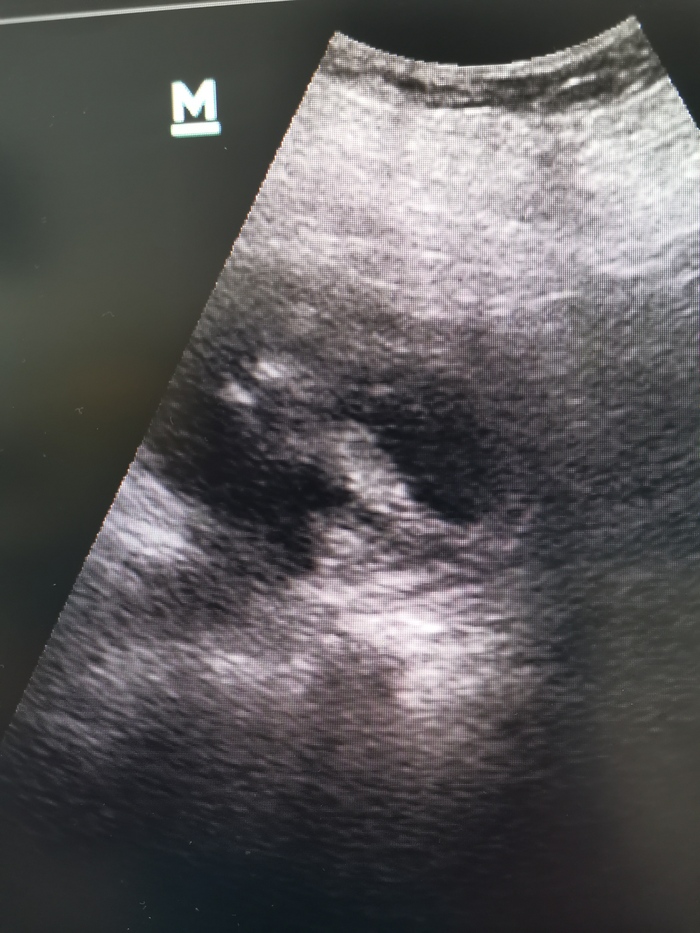

На УЗИ почка особо не изменена (кисты не в счёт). Кроме одного "но". На снимке видно, что как бы вокруг почки имеется жидкостный, достаточно плотный компонент. Вероятно, это кровь, то есть гематома. Факт травмы пациентка отрицает. Или не помнит.